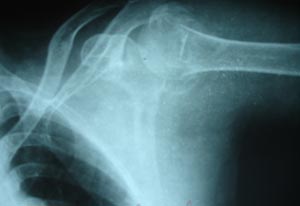

Humerus neck fracture

Fracture of neck of humerus appearing as a step in the cortex.